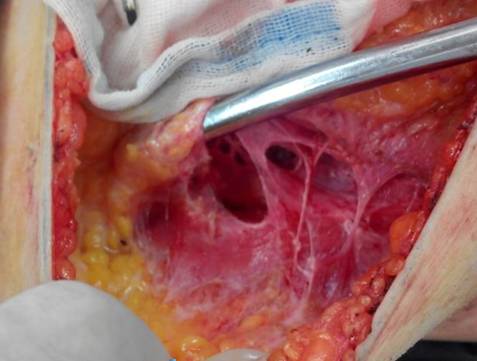

肿瘤外科乳腺疾病诊治中心的赵文和、胡文献医疗团队在反复的科学验证和可行性方案的设定基础上,最终推出我省首例基于脂溶技术的乳腺癌腋窝镂空淋巴结清扫术。该新型手术方式最大的优势在于通过抽吸预先溶解了的脂肪组织,使腋窝手术区域视野异常清晰,区域内血管、神经、淋巴结充分暴露,层次分明,能最大限度的避免手术中血管误切、保留神经、并充分夹闭淋巴管。这种新型手术方式能明显降低乳腺癌腋窝淋巴清扫术后并发症的发生,如患侧上肢淋巴水肿及功能障碍、手术区域感觉异常等。

2013年11月6日,41岁的杨女士接受了这种新型手术方式,当她顺利的返回病房,安静地躺在病床上时,主刀医生胡文献副主任医师向她和家人描述了术中的一些情况。胡医师说:“其实医生在行腋窝淋巴结清扫术时,最担心的是手术视野不清同时病人又有神经血管等解剖位置异常的情况发生,无法尽可能地保留神经血管等结构,导致术后并发症的发生,但你们知道吗,运用了这种新技术后,就好像给医生佩戴了一副3D眼镜,所有的画面层层叠叠,异常清晰,你腋窝的肌肉就像大树,血管和神经就像树干,淋巴结就像长在树上的果实,仿佛伸手就可以摘到。一切都变的非常清晰和奇妙。可以负责地说,这次手术非常成功,将很大程度缓解你术后的不适。并且,你一定要有信心,医学在进步,我们一起加油,一定会战胜病魔!”

基于脂溶法的脂肪组织抽吸后的腋窝镂空图,血管神经淋巴结显示十分清楚